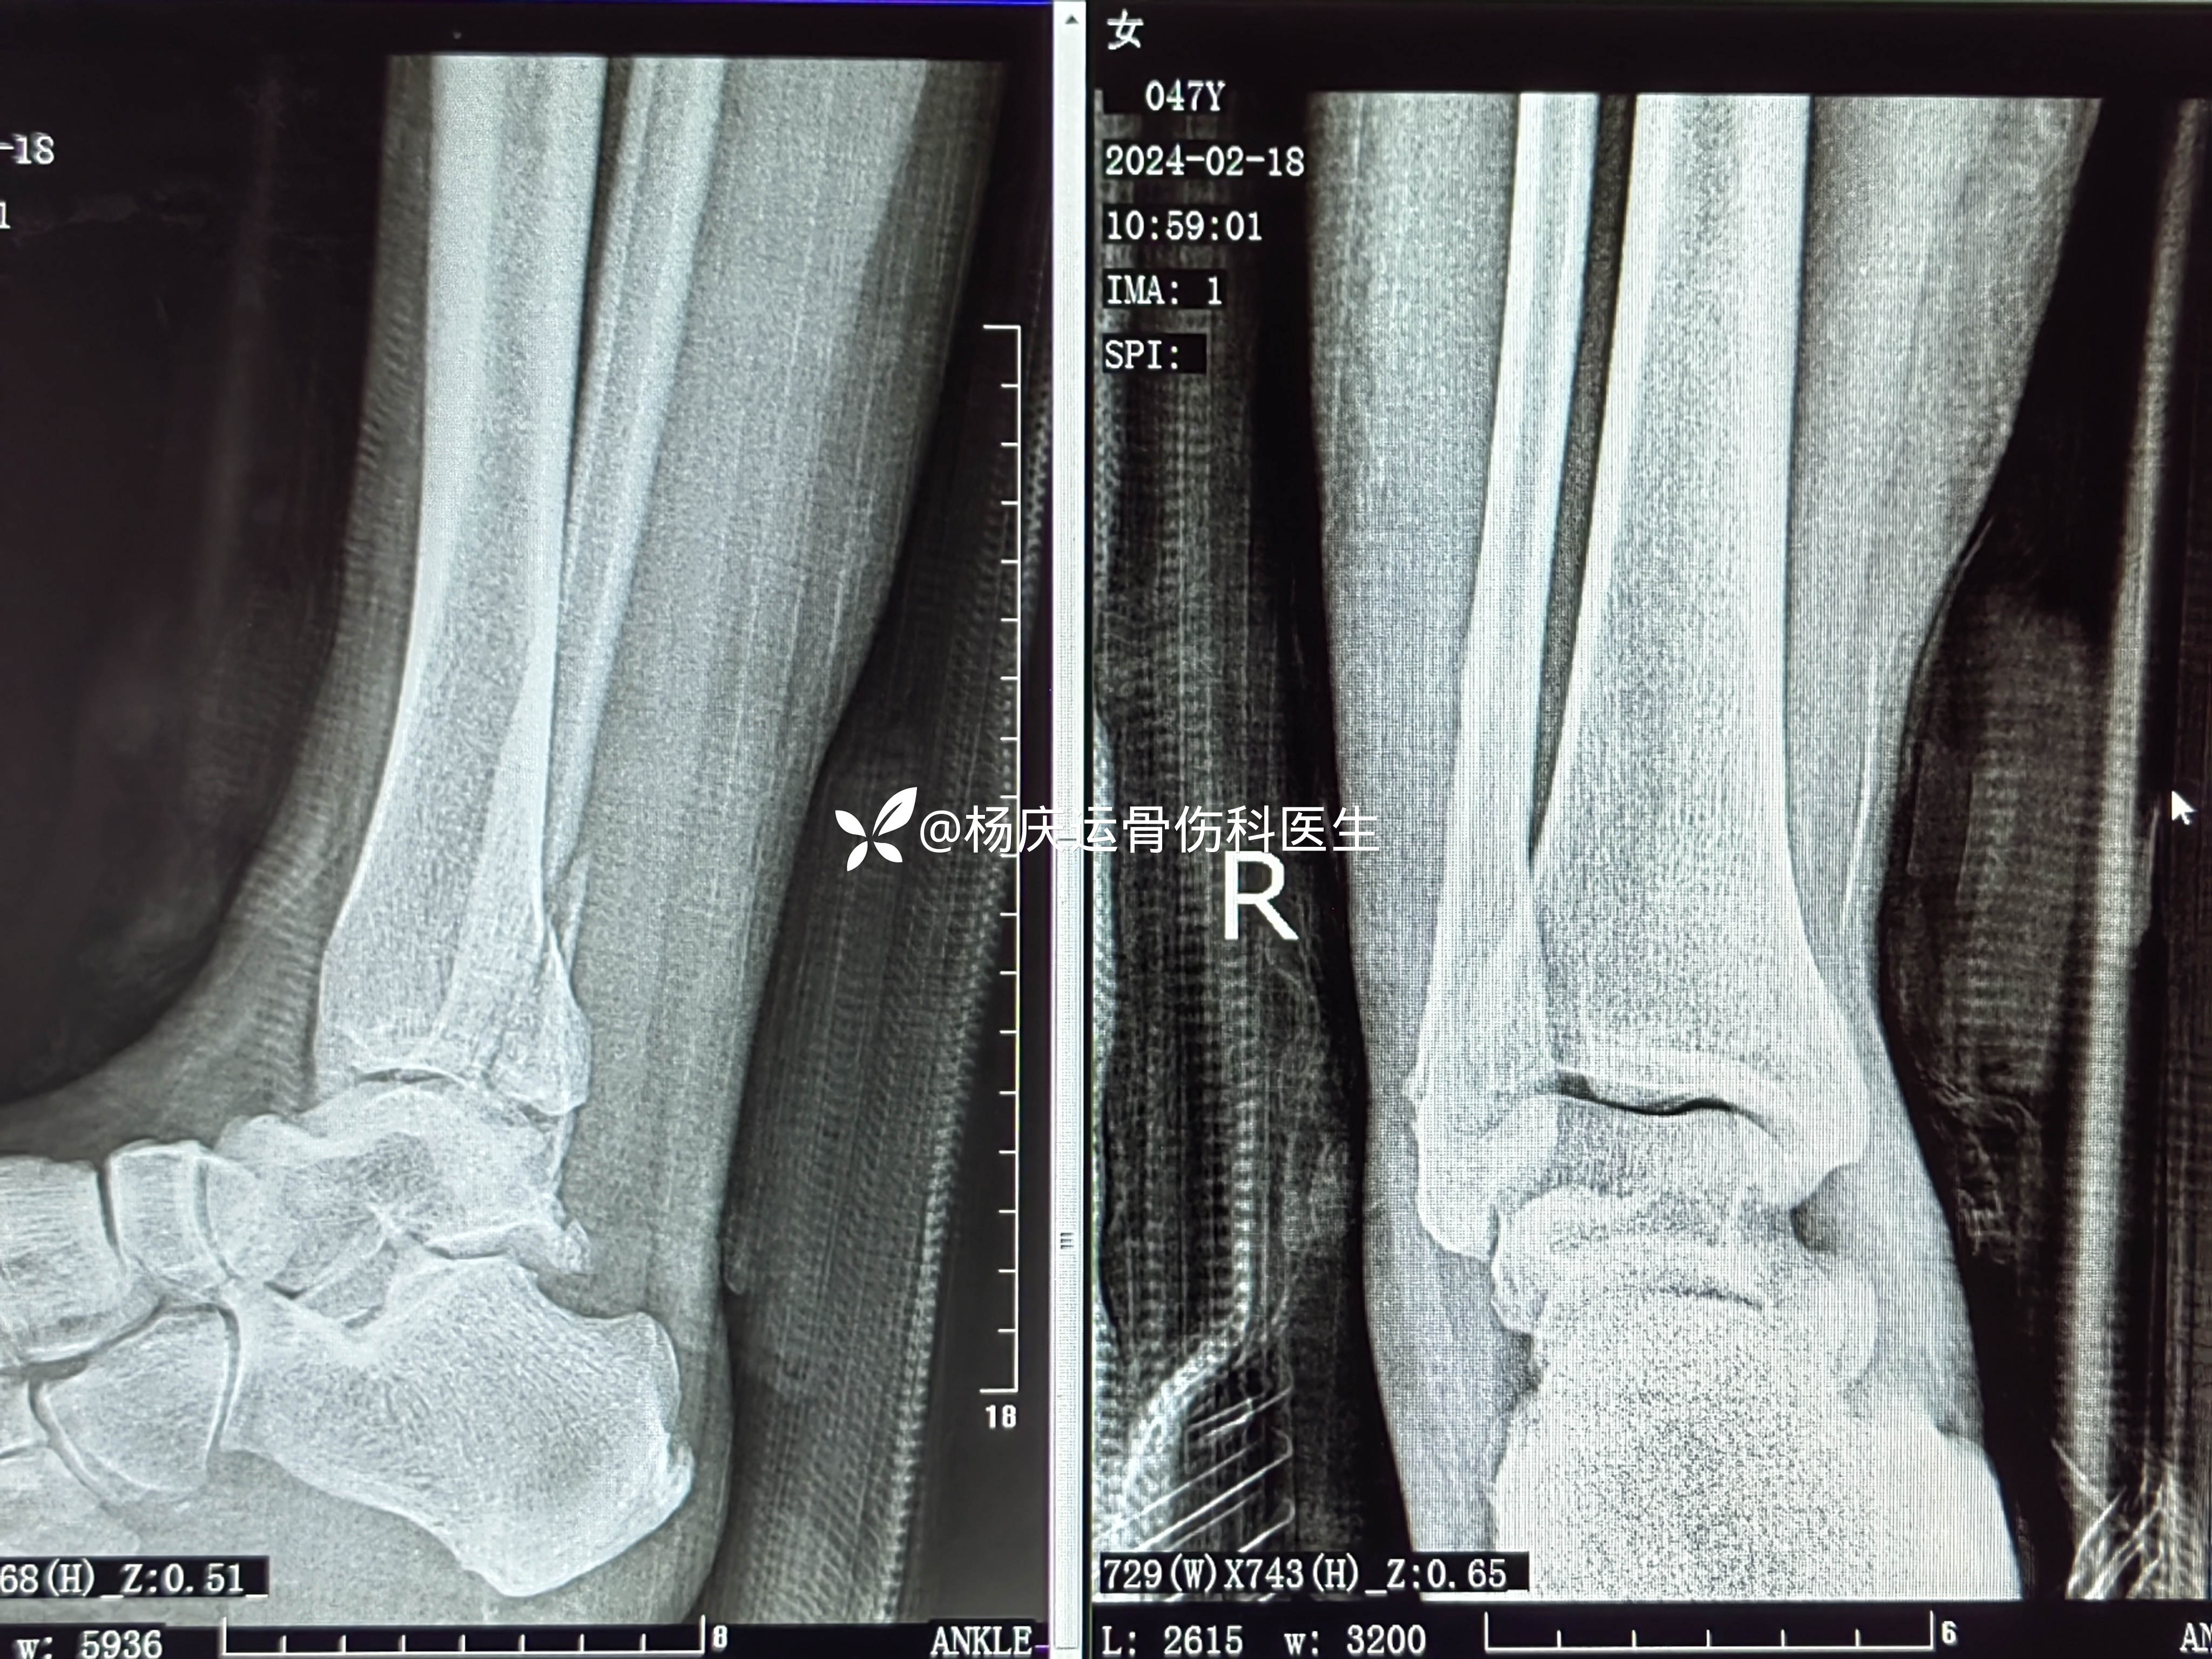

9天复查

19天复查